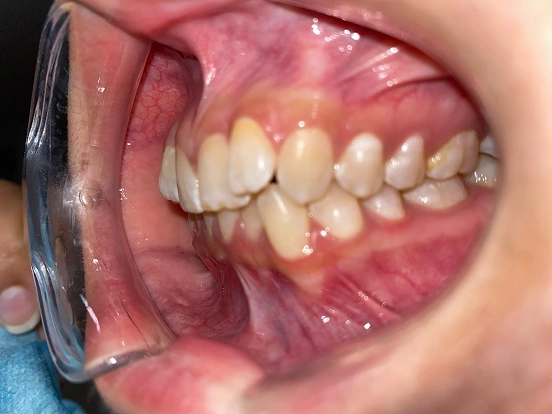

Braces EJ

EJ’s braces journey demonstrates how traditional orthodontics can deliver a complete and lasting smile transformation. The braces effectively corrected spacing and bite issues, leaving behind a perfectly straight, radiant smile that reflects months of dedication.